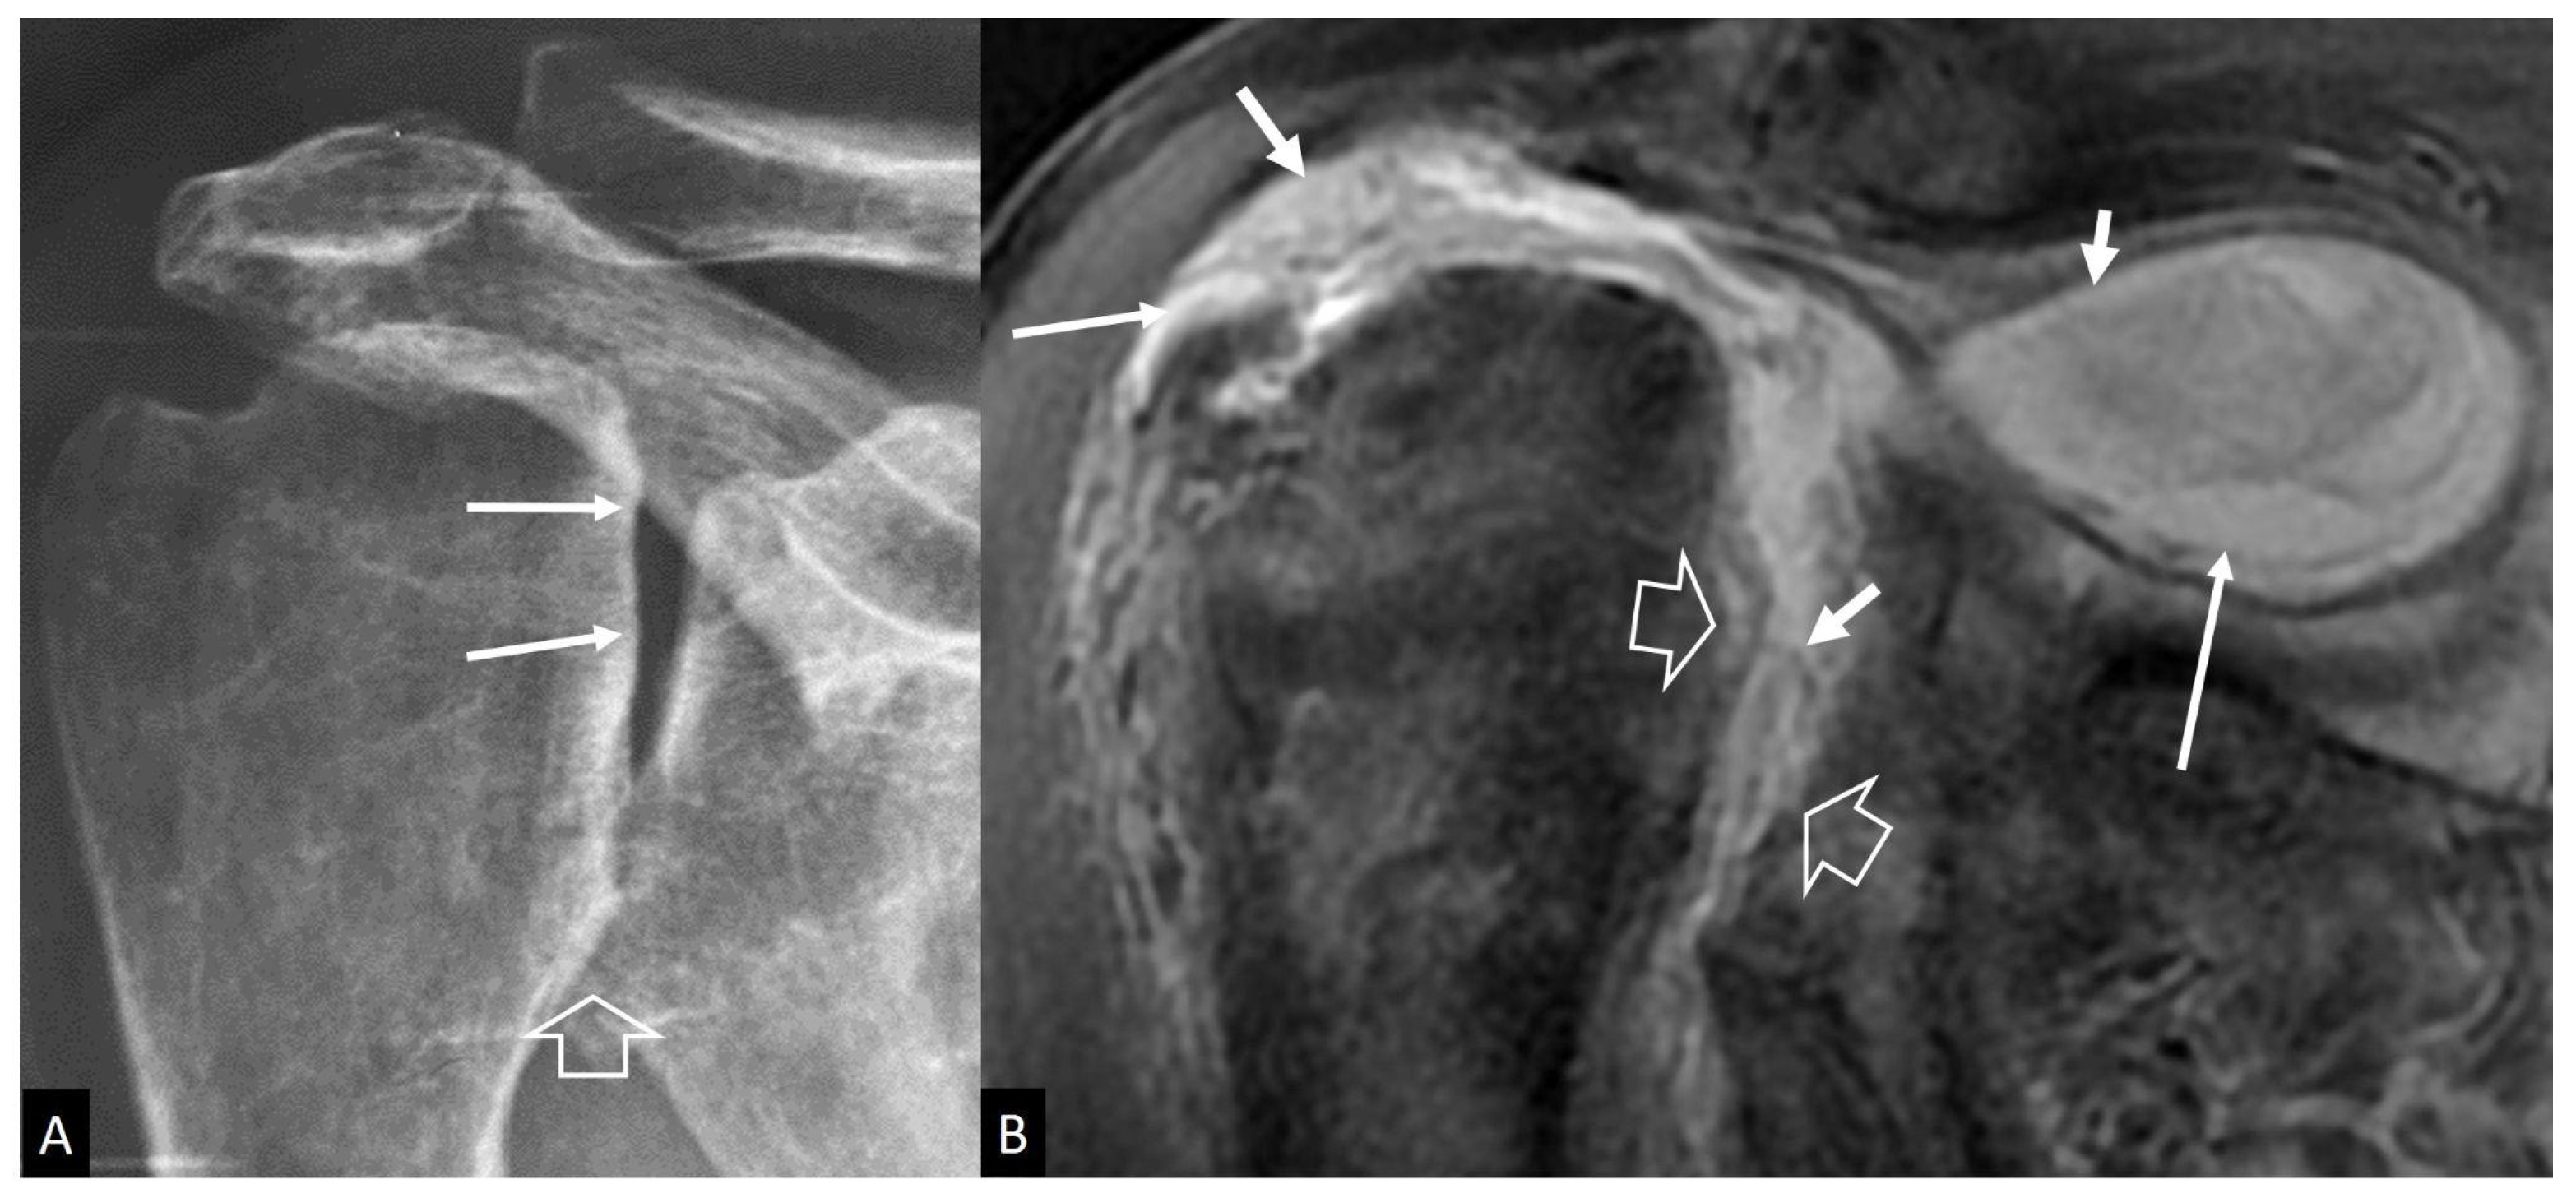

4.2.1. Inflammatory Arthritis

4.2.2. Neuropathic Arthropathy